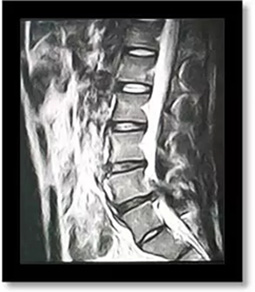

(術前)

劉志安副院長經(jīng)查看MRI(核磁共振成像)結果后,顯示小姚腰5/骶1椎間盤突出,髓核左下方游離,情況已經(jīng)比較嚴重,遂收住入院。